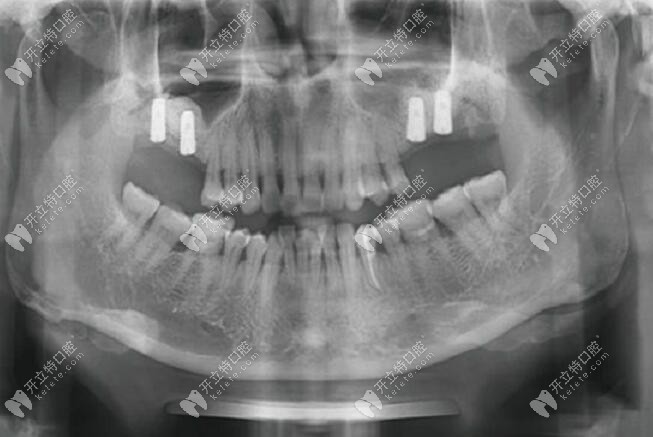

口內(nèi)檢查:16、26、27號牙齒缺失,17號牙齒有3度松動,唇側(cè)及腭側(cè)的牙根暴露;18號牙2度松動,局部牙齦有輕微紅腫,28號牙1度松動。

CBCT片檢查:16號牙位處測量竇嵴距為1.6mm;17號牙齒根尖周的牙槽骨有明顯吸收;26號牙位處測量竇嵴距為1.0mm;27號牙位處測量竇嘴距為1.6mm。

2、二期手術(shù):種植后八個月CT復(fù)查,口內(nèi)牙齦愈合良好、無明顯紅腫、種植體位置良好、上頜竇成骨良好,放置愈合基臺(直徑6mm、5mm,穿齦3mm)。